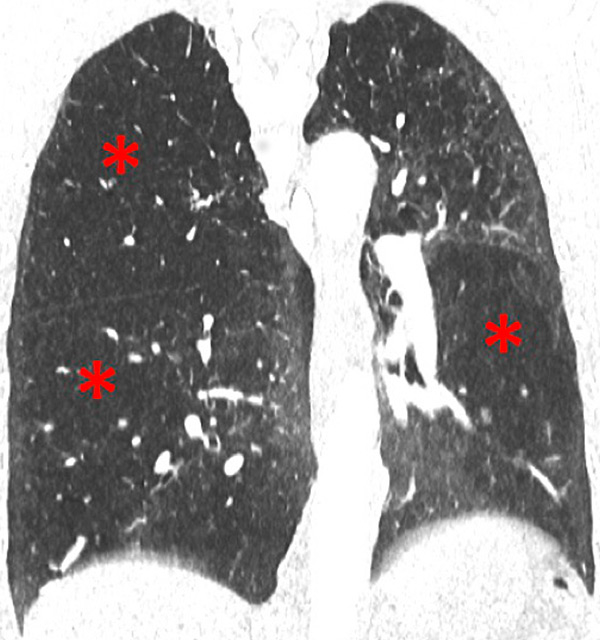

Figure 6

Perfusion heterogeneities in idiopathic pulmonary artery hypertension (stars) in two different patients (A/B). The dilatation of the arteries in pulmonary hypertension (arrows) is not always observed depending on the severity of pulmonary hypertension.

Nowadays, DECT imaging can be used for pathologies other than CTEPH and seems to offer advantages for PH characterisation because different DECT findings have been described in acute pulmonary embolism, CTEPH and idiopathic PAH (IPAH). In fact, perfusion defects are smaller and less defined in PAH than in CTEPH. This is likely due to focal under- and overperfusion as a result of the structural pulmonary vascular changes that occur in PH, which include vascular endothelial damage, cellular proliferation and occlusion in the distal pulmonary vasculature. Perfusion heterogeneities in DECT imaging are also common and seen in most cases of PAH. Findings of perfusion inhomogeneities related PAH have long been recognised in scintigraphy, and often are referred to as having a “mottled” pattern [42]. These perfusion defects are different from those seen in CTEPH, with nonsegmental and poorly defined defects (fig. 5). This heterogeneity is related to the severity of the disease. In PAH, this perfusion variability on scintigraphy is well correlated with pulmonary vascular resistance, as Talwar et al. showed [43]. Recently, similar results were published for DECT techniques (fig. 6). Ameli-Renani et al. described an increased enhancement of pulmonary arteries with reduced iodine lung perfusion in PH, and a good correlation of DECT perfusion heterogeneities with pulmonary vascular resistance; they showed a greater heterogeneity in parenchymal iodine maps in PH without pulmonary embolism [13]. The authors concluded that perfusion heterogeneities seen in DECT appear to be a direct reflection of pulmonary vascular resistance.